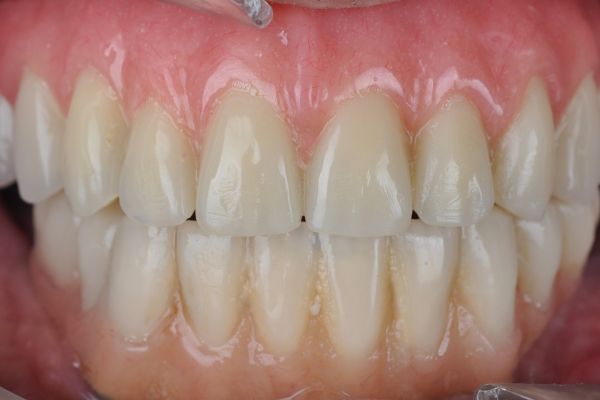

As best clinical case, Garrido Martínez, et al. are the first winners with an excellent clinical case on the maxillary reconstruction of a patient with subperiosteal implants. Anitua repeats the award with a clinical case where they successfully show the explantation of a poorly positioned implant in the aesthetic sector and its subsequent regeneration.